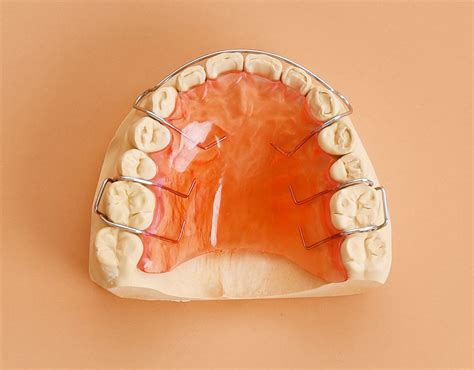

Retenedor Hawley

Este tipo de soporte está hecho de alambre plegable y acrílico o plástico. El alambre pasa por delante de los dientes y el acrílico tiene una forma tal que encaja perfectamente en la boca. Los soportes Hawley están disponibles en una variedad de colores y estilos, con lo cual puedes personalizarlos cuando quieras. Además, este tipo de retenedor es ajustable, por lo que tu ortodoncista puede «afilar» tus dientes un poco después de que los frenos se ajusten.

Probablemente sea el aparato más común de los retenedores removibles, y puede ser utilizado tanto para la arcada superior como para la inferior. La placa clásica de Hawley se compone de retenedor de Adams para los molares de 0,025 o 0,030 pulgadas, un arco vestibular de 0,028 o 0,035 pulgadas, que contacta con la superficie vestibular de los caninos y de los cuatro incisivos, y el cuerpo de acrílico que se adapta a los tejidos blandos y a la superficie lingual de los dientes, además de servir como método de unión.

Ventajas y Desventajas del Retenedor Hawley

- Ventaja: ajustable. Permite que los dientes se toquen entre sí de forma natural. Dura mucho tiempo con el cuidado adecuado. Fácil de limpiar.

- Desventaja: altamente visible. Puede que te sientas un poco apático al principio cuando lo uses.